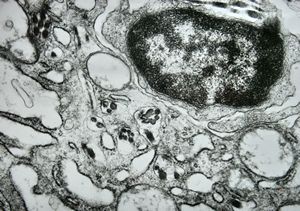

F, 24y. | molluscum contagiosum … virions

F, 24y. | molluscum contagiosum

F, 24y. | molluscum contagiosum

F, 7y. | molluscum contagiosum … virions

F, 7y. | molluscum contagiosum … virions

F, 24y. | molluscum contagiosum … virions